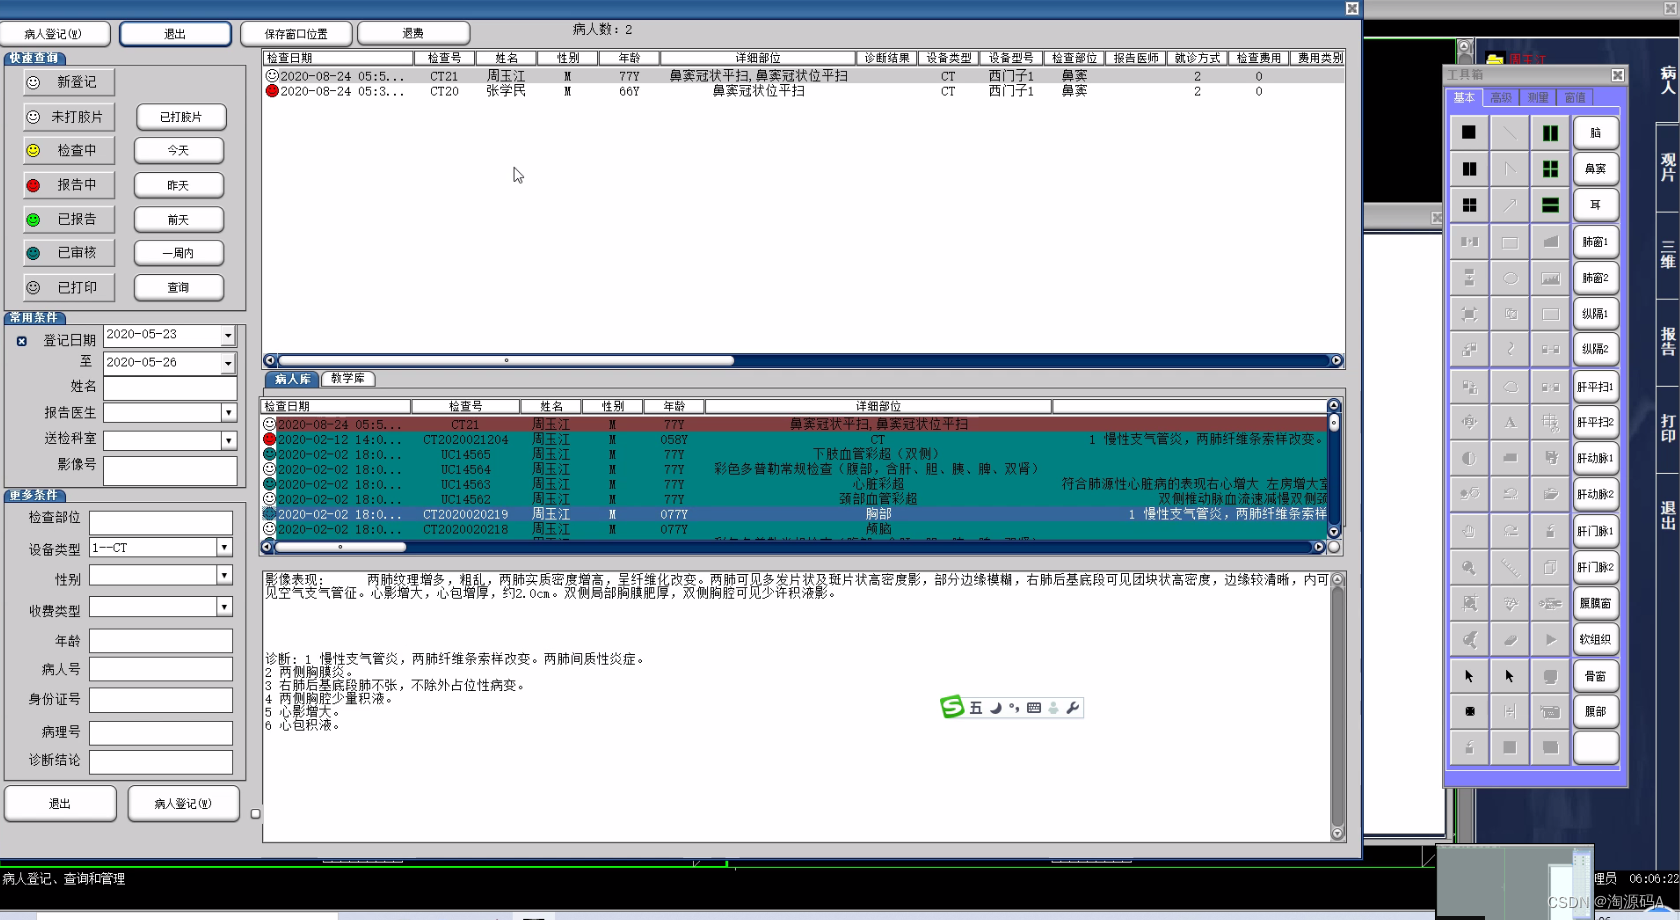

登记系统

实现与HIS系统的连接,从HIS系统提取患者相关信息后,登记病人资料,并可扫描检查申请单;

实现DIC M W RKLIST服务,在检查登记后,自动将中文信息转换为英文,单个或批量将检查清单传送给影像设备;

病人检查排队叫号。

图像及病历检索查询

根据检查号、门诊/住院号、姓名、检查部位、疾病诊断、日期范围、申请科室、报告医生等条件查询申请、报告或图像。

支持模糊查询功能,组合查询等高级查询。